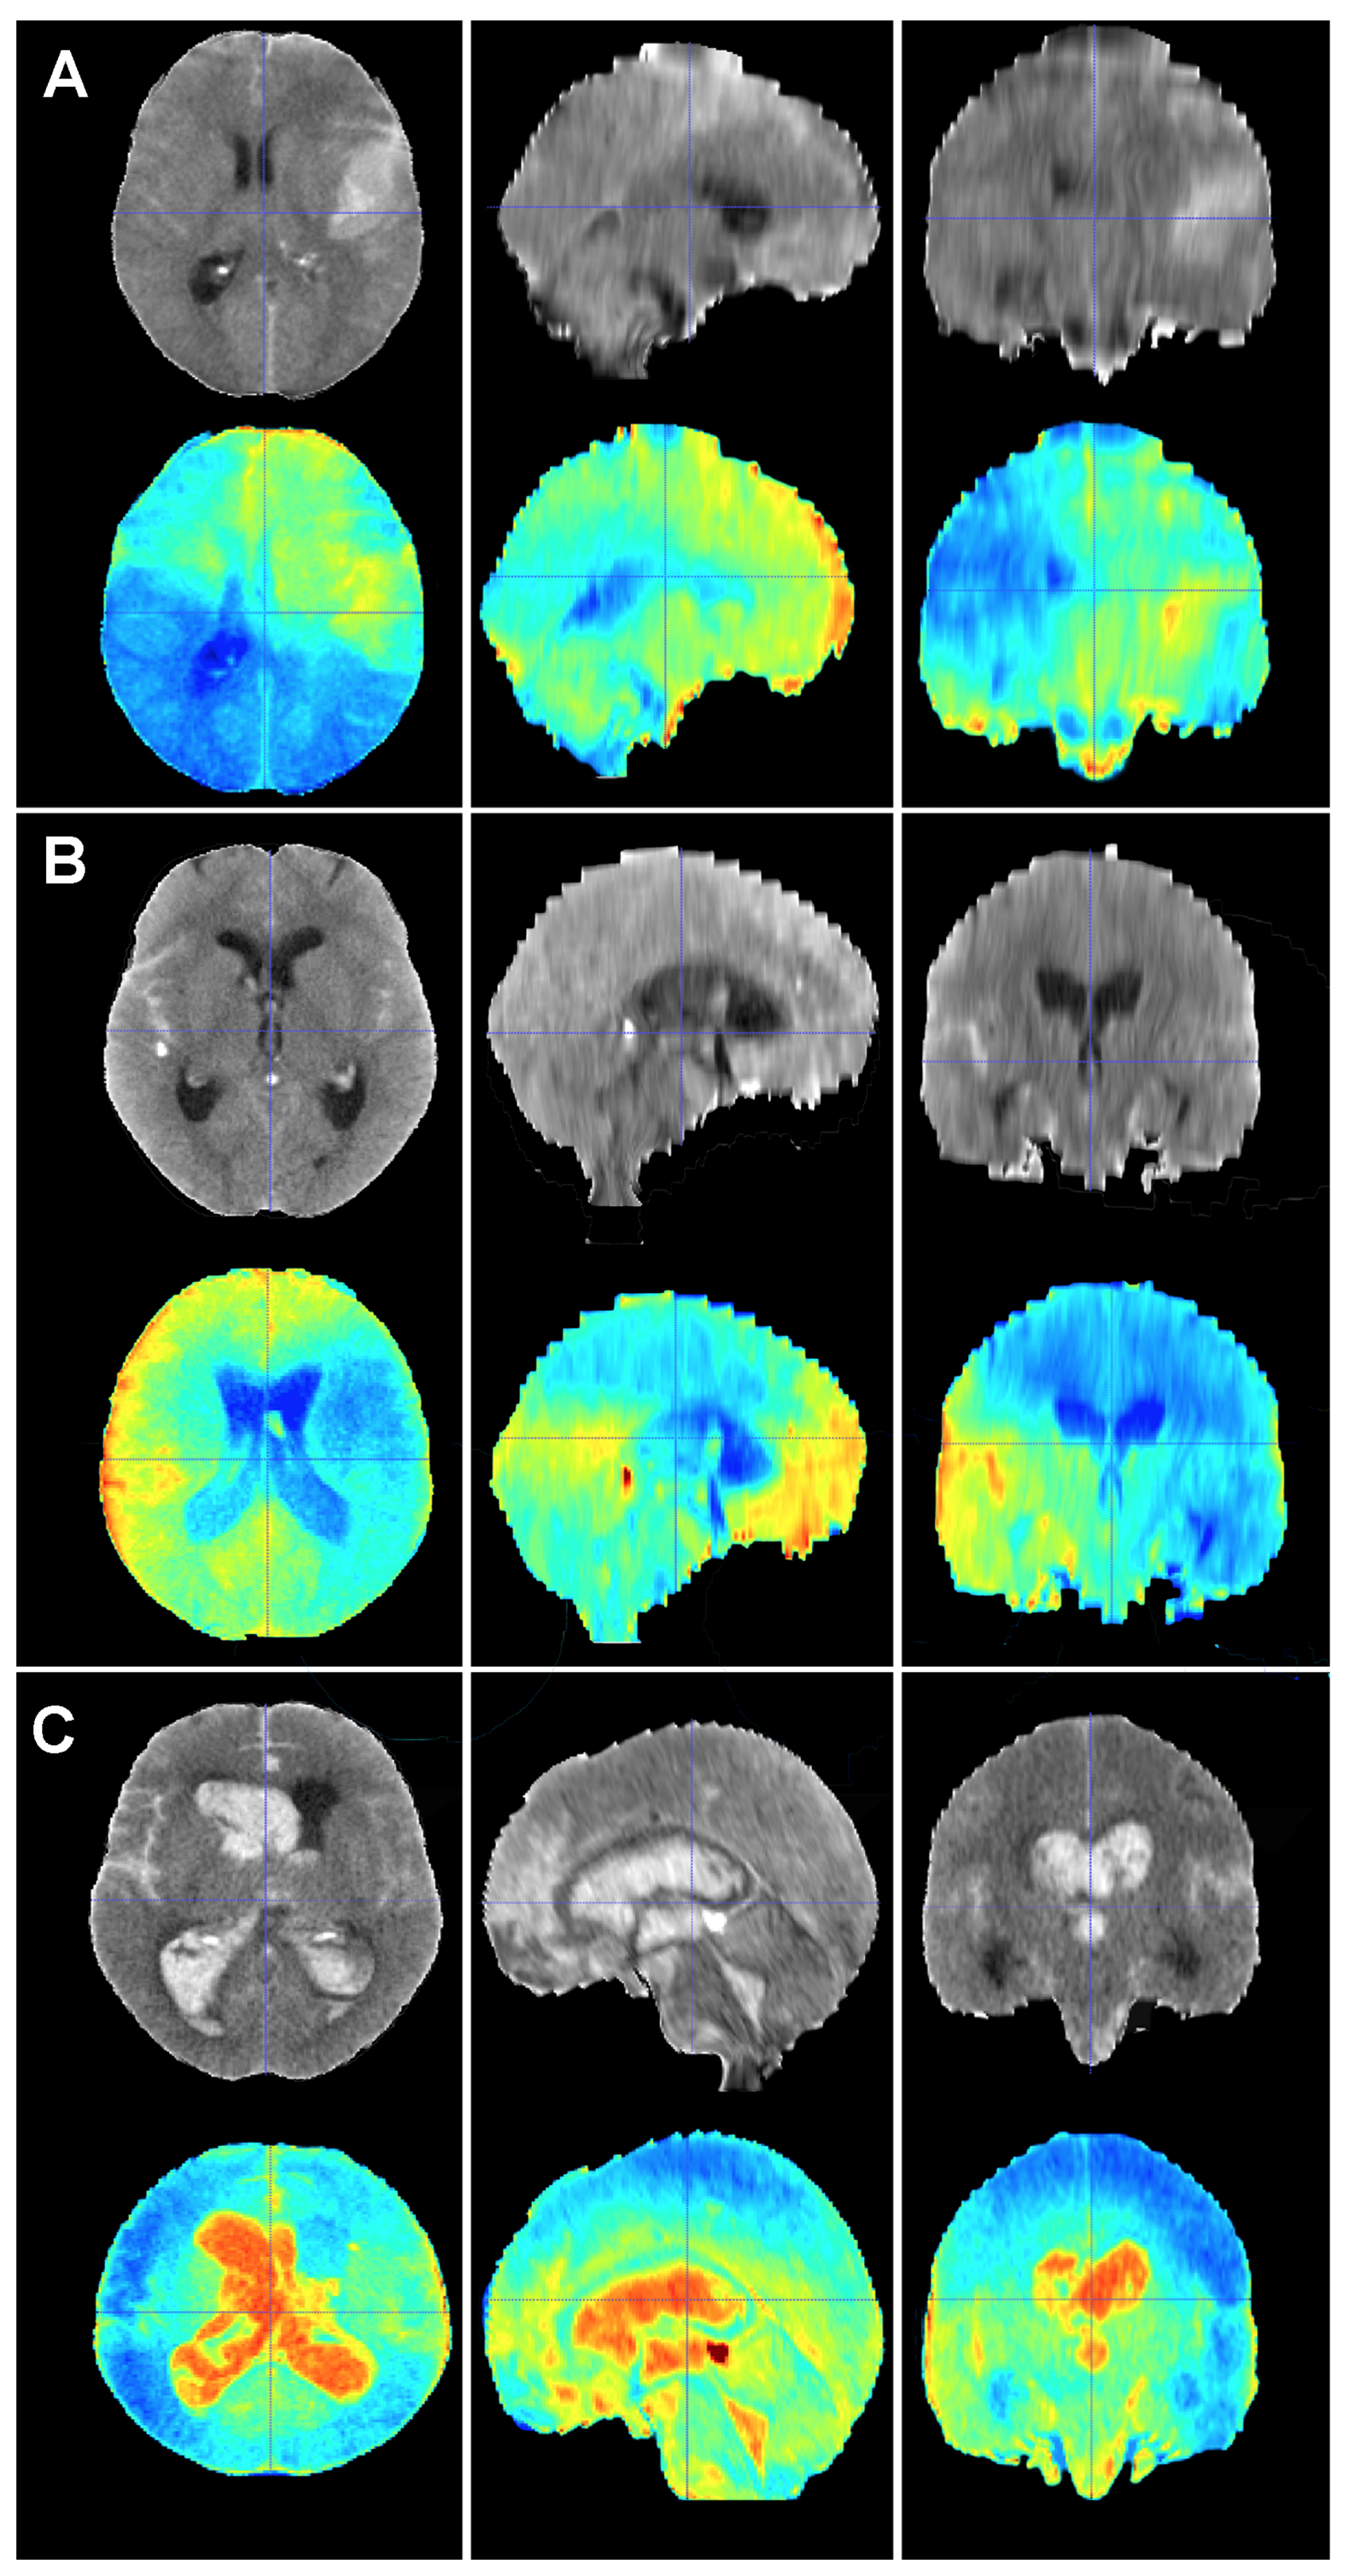

Figure 6.

Baseline CT scan (upper row) and gradient-weighted class activation mapping or Grad-CAM (lower row) for three patients (A–C) from the test cohort who died as a result of a subarachnoid hemorrhage (SAH). These maps visually illustrate the areas the model considered to allocate patients into the “dead” group. Grad-CAM maps show that posterior fossa and intraventricular and cisternal blood might be relevant areas or items to consider in order to classify patients as dead. (A) A 51-year-old male who suffered a SAH due to the rupture of a left middle cerebral artery aneurysm. The patient initially presented with a WFNS grade 2, but abruptly deteriorated to a WFNS grade 5 requiring emergent surgical treatment. The patient died on postoperative day 56 as a consequence of both systemic and neurological complications. (B) A 70-year-old female who was diagnosed with a SAH caused by a right posterior communicating artery aneurysm who died 40 days after her admission due to a combination of factors, including delayed cerebral ischemia, meningitis and pneumonia. (C) A 78-year-old male with a SAH caused by an anterior communicating artery who was admitted to the hospital with a WFNS grade 5 and an mF grade 4 who died the next day after the event.